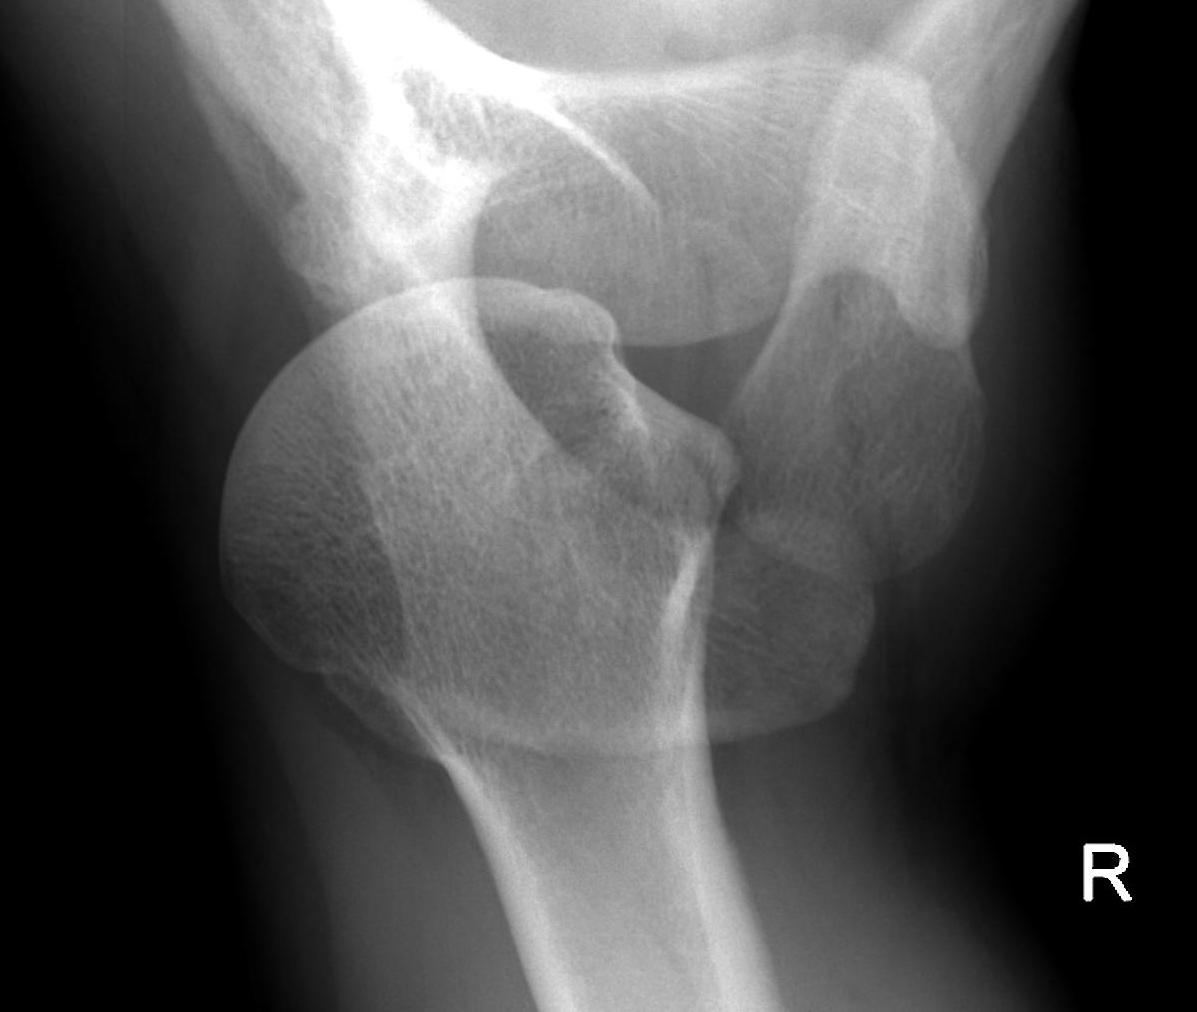

Axillary Xray

Diagnostic - humeral head posterior to glenoid with evidence of reverse Hill Sachs

CT scan

Confirms dislocation

Reverse Hill Sachs

Humeral head defect

- caused by impaction of anterior humeral head on posterior glenoid

- intra-articular

- measured as a percentage of the articular surface

Lesser tuberosity fractures

Posterior glenoid fractures / bony bankart